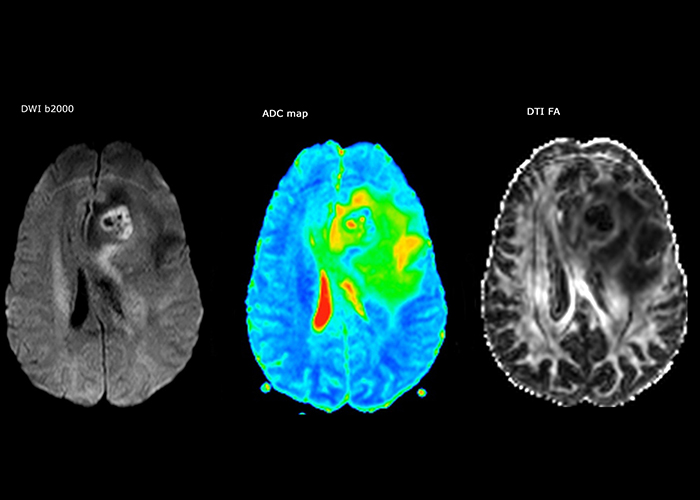

Comprehensive exam answers complex brain tumor questions

Dr. Savatovsky uses five or six different ExamCards for imaging a mass or a known tumor in the brain. “If there is a mass in the brain we try to characterize it to inform the neurologist for determining next steps or to help neurosurgeon prepare for a surgery or biopsy. For follow-up after treatment we have different protocols for different treatments and we adapt for intra- or extra-axial tumors.”

“The biggest challenges are properly characterizing the lesion and giving the surgeon all the information needed, such as the location of vessels and functional areas. Sometimes a very comprehensive exam is necessary, such as when a mass has been discovered at another hospital after which the patient is referred to us. We then do both lesion characterization and preoperative imaging in one exam, so both morphologic and functional assessment. For morphologic assessment we will use pre- and post-contrast T1-weighted imaging, FLAIR to assess infiltration, and diffusion. For functional characterization we will perform perfusion, spectroscopy, and susceptibility weighted imaging to look for micro vessels or micro hemorrhage inside the lesion[4]. For preoperative imaging we perform specific morphologic imaging that is compatible with the navigation system; depending on the location of the tumor, we would do fMRI or DTI.”

“That is the most comprehensive exam we would do. Ingenia has the good spatial resolution and high SNR to provide all this information, and the flexibility to use shorter sequences, so we can do a very comprehensive examination in a limited time.”